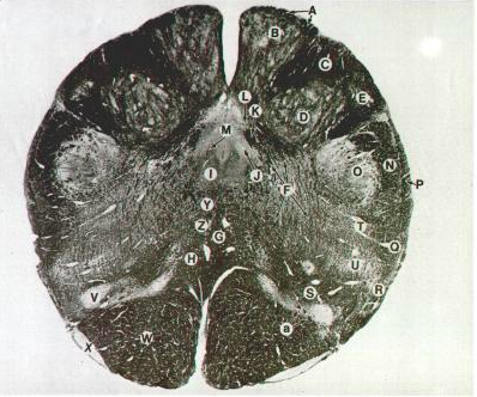

H

Medial Lemniscus (decussation)

W

Corticospinal

Y

MLF

P, Q

posterior spinocerebellar

A, B

Nucleus Gracilis

C, D

Nucleus Cuneatus

Medial Leminiscus